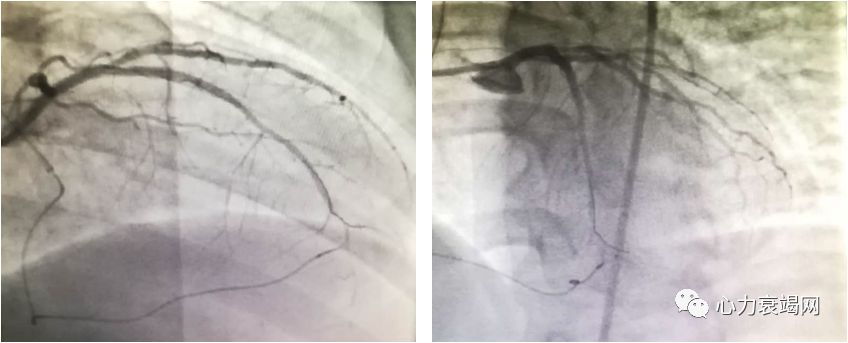

➤ 介入治疗

冠状动脉介入治疗

于前降支病变处置入2枚支架